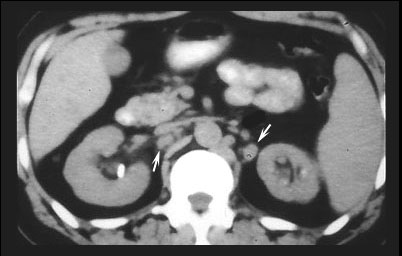

Hepatomegaly and splenomegaly occur in about one-third of patients. Liver lesions have been found in about 5% and spleen lesions 2-3 times as often in patients with sarcoidosis undergoing computed tomography examinations. The liver and spleen lesions most often appear as small widespread foci of decreased attenuation best seen when intravenous contrast material is utilized.

ABDOMINAL LYMPHADENOPATHY SPLEEN & LIVER GRANULOMAS

The small low attenuation lesions in the liver and spleen in sarcoidosis.